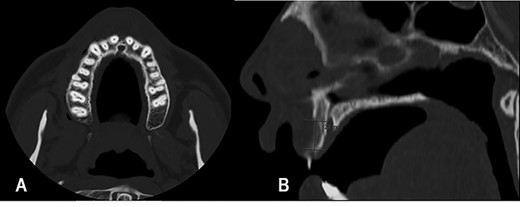

The typical biphasic pattern of MCS, composed of islands of cartilage (*) admixed with poorly differentiated small round cells with scant cytoplasm (#). H&E stain.

Diagnosis of MCS can only be established by histopathological examination, characterized by a biphasic pattern, with a sheet-like or patternless proliferation of small differentiated spindle or round cells surrounding discrete nodules of differentiated hyaline cartilage [3].